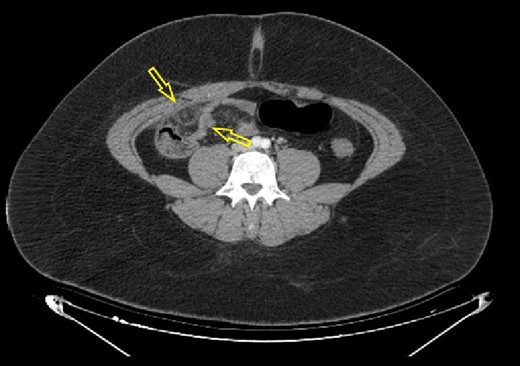

A 16-year-old female patient with obesity class III (body mass index of 41.5) presented to the emergency ward with abdominal pain for the last 48 h. No other comorbidities or previous abdominal surgery were reported. Physical examination was positive for lower right quadrant abdominal pain and for signs of local peritonism. The patient did not report loss of appetite, nausea, or vomiting. Laboratory analysis showed elevated serum levels of glycaemia of 6.48 mmol/l (normal range of 3.90–5.83 mmol/L) and C-reactive protein level of 63.30 mg/L (normal range of 0.00–5.00 mg/l). Abdominal ultrasonography failed to conclude the presence of intra-abdominal condition. Abdominal computerized tomography (CT) scan showed inflammation in the surrounding fat tissue of the pericecal region (Figs 1 and 2). No CT signs for acute appendicitis were present. Due to diagnostic uncertainty, an explorative laparoscopy was performed. Intraoperatively, a partial infarction of the right part of the great omentum was seen (Fig. 3). It was resected with a bipolar device (Video supplement S1) and appendectomy was performed additionally. Resected omentum and appendix were extracted via the umbilical port with minimal extension. The operative time was 65 min.

Axial abdominal CT scan (native series) showing intra-abdominal fat inflammation in the pericecal region (arrows).